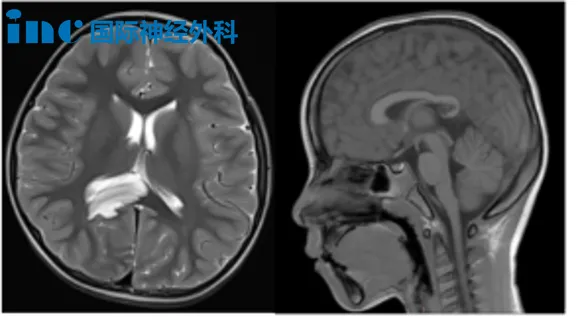

霖霖意外查出脑瘤——右侧海马、右顶叶占位没有带来明显症状。考虑到孩子年龄太小,家人最初选择了保守观察。然而,这颗潜伏的“肿瘤怪兽”并未真正沉睡,它只是在暗中蓄力,伺机而动。

不到一年时间,霖霖的丘脑已被逐渐增大的肿瘤步步紧逼、推挤——露出狰狞面目的肿瘤,还能继续观察吗?

10月22日,霖霖父母带着孩子前往苏州大学附属儿童医院,与巴教授面对面交流。面对父母的疑惑,他解释道:“这种肿瘤不会自行停止生长,一年后复查时会变大。另一个问题是,这类肿瘤可能会发生基因变化,转变为更恶性的类型。而且肿瘤靠近颞叶内侧部,这一部位的肿瘤容易诱发癫痫发作……”

它悄然潜入8岁小航的大脑,盘踞在右侧丘脑与基底节区。初次发现时,肿瘤已显露出不容小觑的规模——病灶大小约4.0cm×4.7cm×4.8cm,高度怀疑为弥漫中线胶质瘤,并引发了梗阻性脑积水。在这幼小的头颅中,肿瘤开始悄然作恶:小航出现记忆力减退、注意力难以集中,甚至喝水时呛咳。